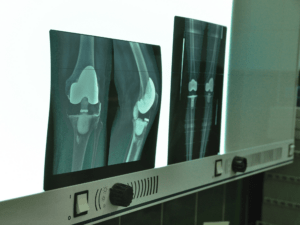

Endoproteza stawu kolanowego to implant zastępujący zniszczone powierzchnie stawowe. W trakcie operacji usuwa się uszkodzone fragmenty stawu i zastępuje je elementami wykonanymi z metalu i specjalnego tworzywa sztucznego odpornego na ścieranie.

To najczęściej wykonywany zabieg. Polega na wymianie powierzchni stawowych kości udowej i piszczelowej (rzadziej dodatkowo rzepki). Stosuje się ją w przypadku bardziej zaawansowanych i rozległych zmian.

Polega na wymianie mniejszej uszkodzonej części stawu, jednego przedziału, najczęściej przyśrodkowego, rzadziej rzepkowo-udowego czy bocznego. Może być zastosowana wyłącznie u wybranych pacjentów, u których pozostałe struktury kolana są zachowane w dobrym stanie.